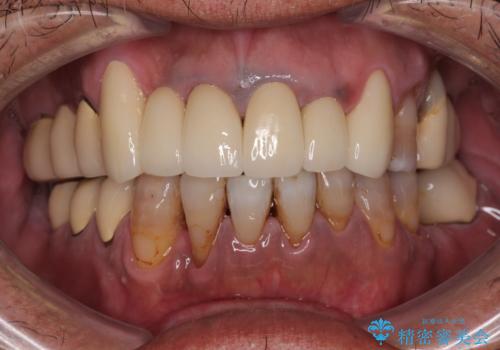

仮歯での期間が長かったとのことでしたが、当院での治療開始後はあっという間に綺麗な前歯に仕上がり、患者様には大変満足していただけました。

仮歯が不適合で歯肉が腫脹していたため、しっかりと調整した新しい仮歯にして腫れを改善した上で、オールセラミッククラウンにて補綴することとしました。

仮歯の隣の歯も詰め物の範囲が広く、仮歯をセラミックに置き換えても統一感のない口元となってしまうため、相談の結果、前歯6本をオールセラミッククラウンにて補綴治療を行うこととしました。